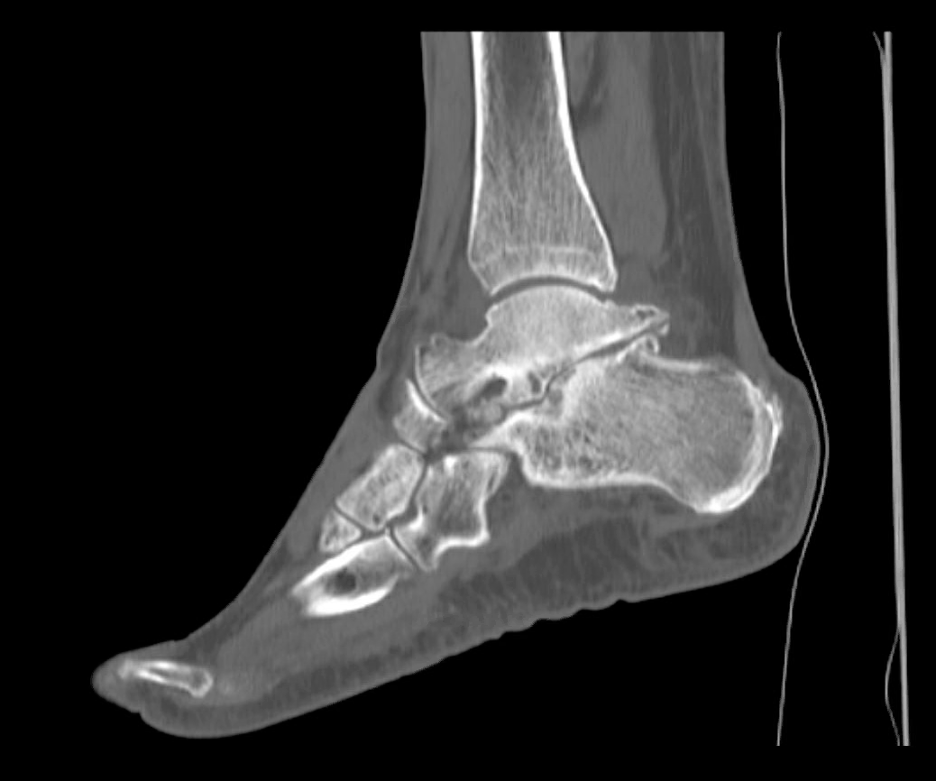

Radiographs showed osseous masses on the lateral aspect of the sinus tarsi and under the fibula with arthrosis of the STJ (Figure 1). The preoperative lateral Meary’s angle was 14º, talar declination angle was 12º, and talocalcaneal angle was 22º. Computed tomography showed arthrosis of the STJ arthrosis involving the posterior facet of the STJ with loss of talar height (Figure 2).